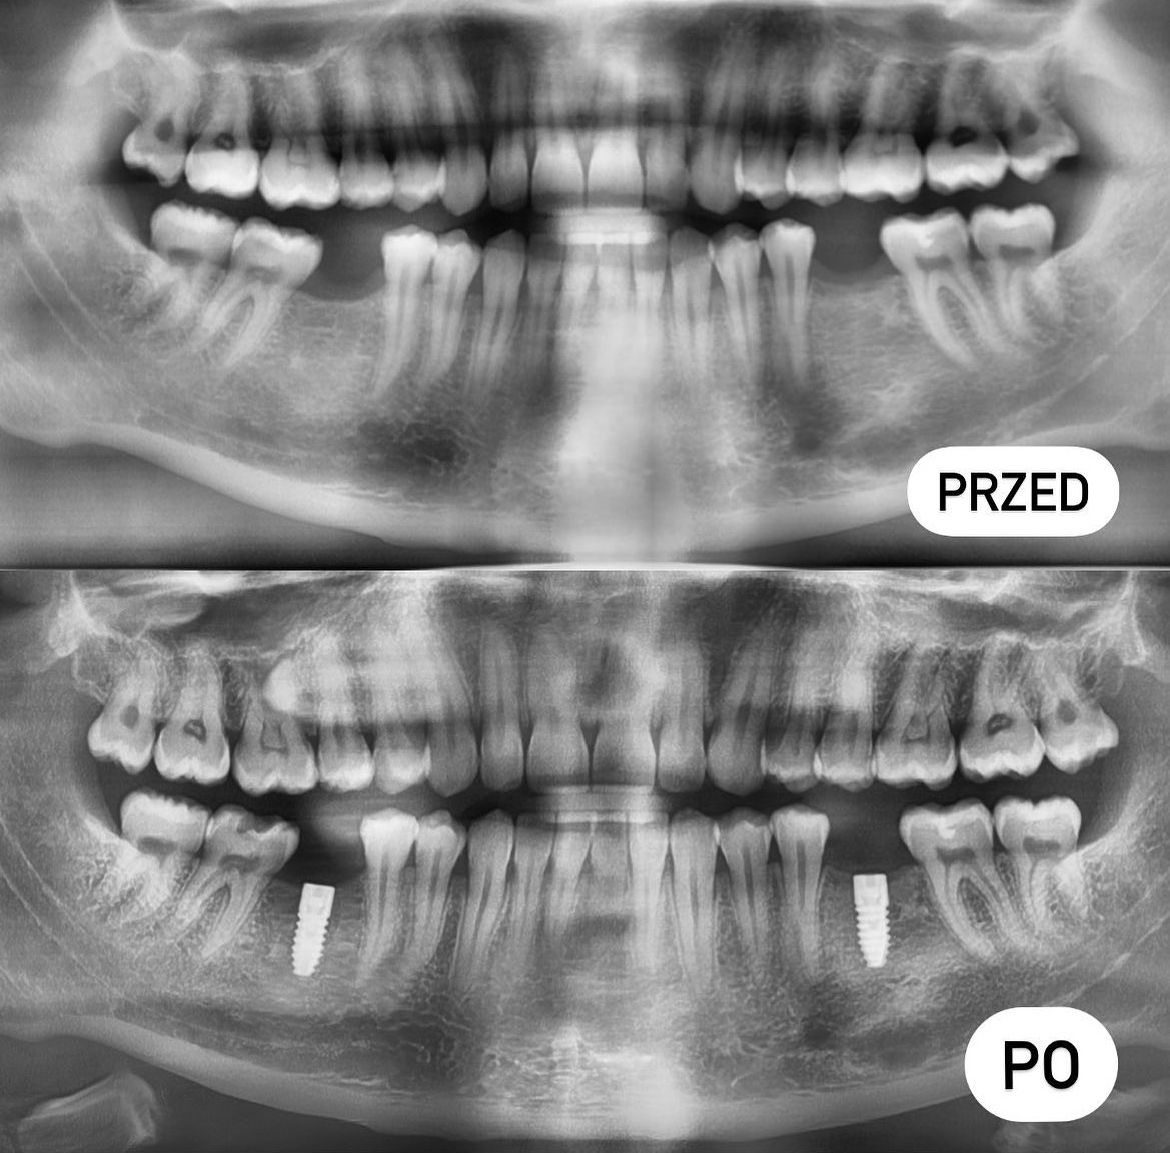

- protetyka (korony ceramiczne (cerkon, E-max), licówki, mosty, protezy ruchome, korony na teleskopach, inlay, onlay, overlay, endkorony);

- implantologia,

Leczenie z wykorzystaniem nowoczesnego sprzętu i najnowszej wiedzy medycznej. Kompleksowe plany leczenia z uwzględnieniem potrzeb i oczekiwań pacjenta. Współpraca z najlepszymi specjalistami. Pełna diagnostyka na miejscu- pantomogram, tomografia komputerowa, zdjęcia zębowe, zdjęcia skrzydłowo-zgryzowe.